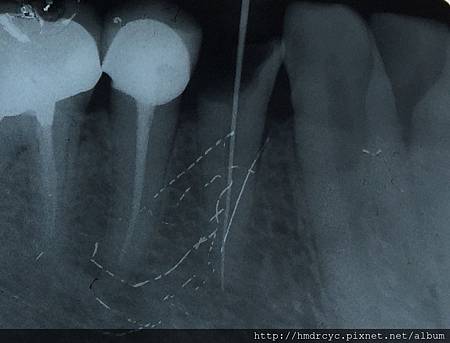

2. 測量根管長度

6. 牙膠緻密封填